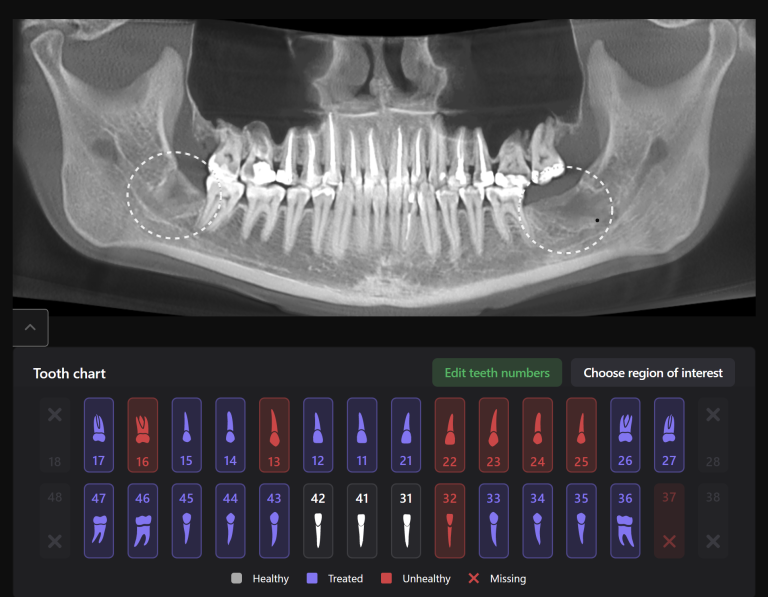

Task: Plan the implant treatment for the replacement of teeth 16 (Universal 3) and 17 (Universal 2), reduce the time required for surgical template fabrication, and improve the accuracy of its fit. Using the “STL” module of Diagnocat, it is possible to create a 3D reconstruction of cone-beam computed tomography (CBCT) and virtual models of templates. To achieve this, intraoral scan data is uploaded into the module, and a suitable CBCT is selected for merging.

Problem:In some clinical cases, it’s difficult to ensure the required accuracy in merging intraoral scanning and CBCT.

Solution: Diagnocat AI provides an advanced solution for identifying CBCT structures using machine learning and artificial intelligence technologies. By combining STL and DICOM data in a unified coordinate system, Diagnocat minimizes errors when creating template models.